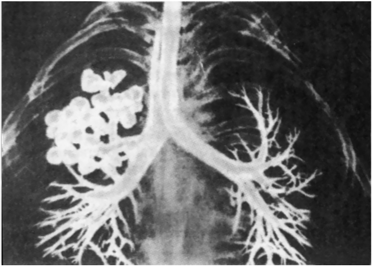

Сг легкого

Сг легкого 109 фото